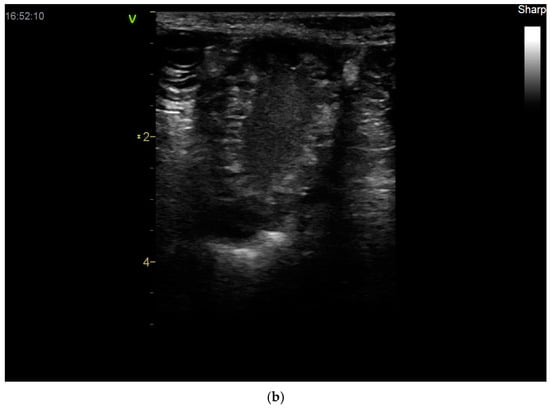

- Bigliardi, E.; Parmigiani, E.; Cavirani, S.; Luppi, A.; Bonati, L.; Corradi, A. Ultrasonography and Cystic Hyperplasia-Pyometra Complex in the Bitch. Reprod. Domest. Anim. 2004, 39, 136–140. [Google Scholar] [CrossRef] [PubMed]

- Quartuccio, M.; Liotta, L.; Cristarella, S.; Lanteri, G.; Ieni, A.; D’Arrigo, T.; De Majo, M. Contrast-Enhanced Ultrasound in Cystic Endometrial Hyperplasia–Pyometra Complex in the Bitch: A Preliminary Study. Animals 2020, 10, 1368. [Google Scholar] [CrossRef] [PubMed]

- Younis, M.; Mohammed, F.F.; Ragab, R.S.; Gohar, H.M. Ultrasonography and Pathological Evaluation of Cystic Endometrial Hyperplasia Pyometra Complex in Bitches and Queens with Related Ovarian Alterations. Glob. Vet. 2014, 13, 60–67. [Google Scholar]